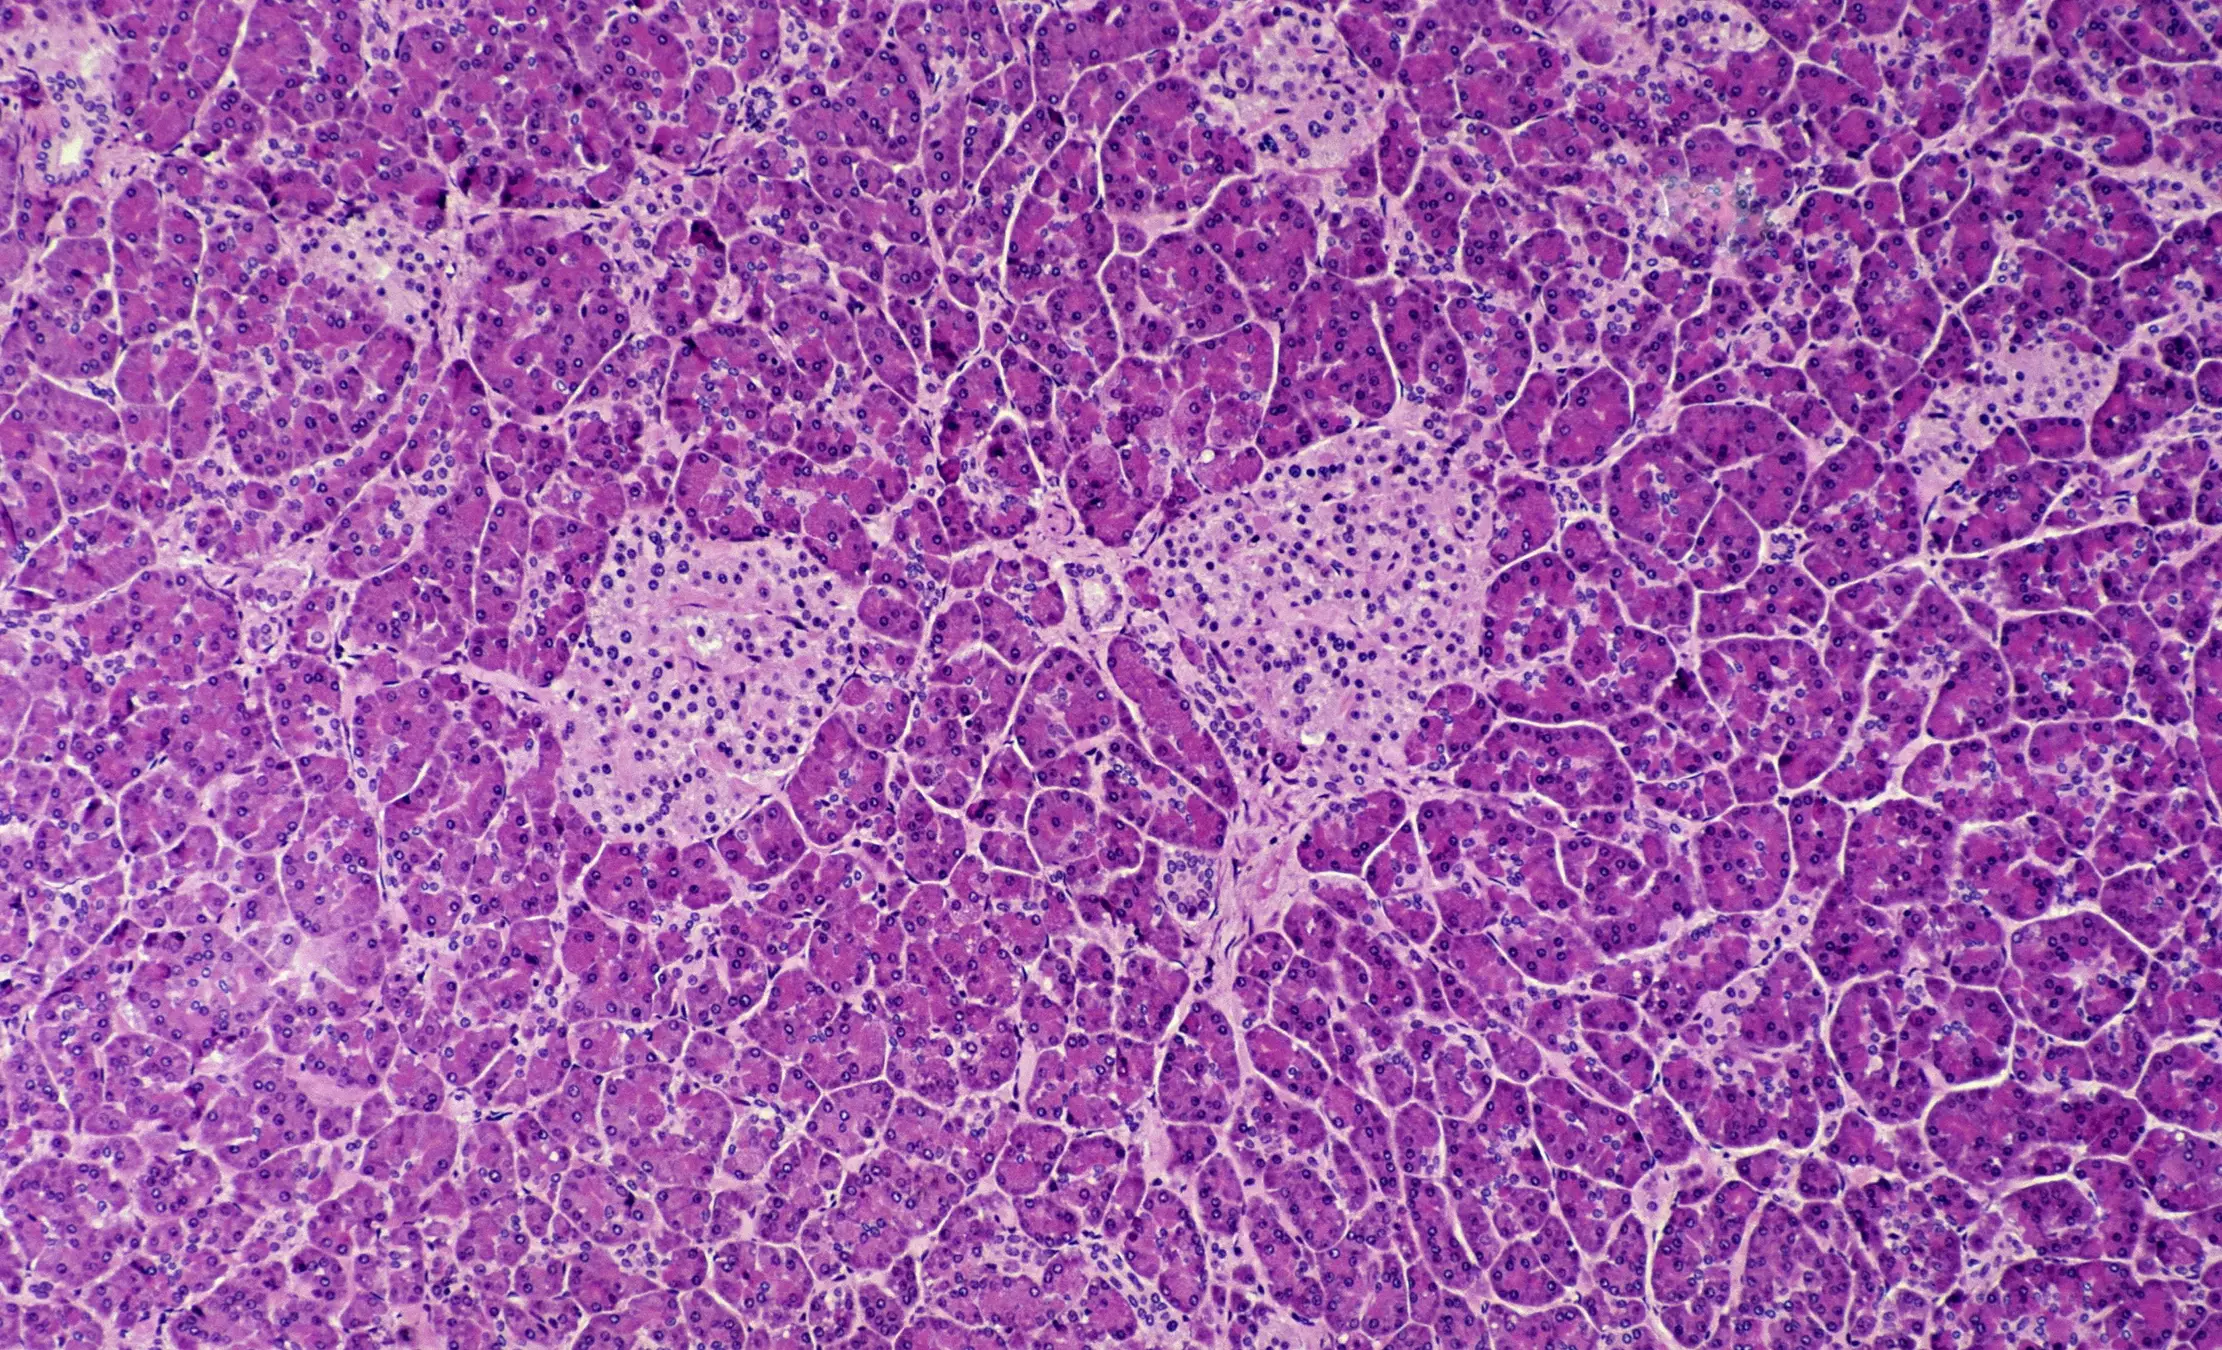

As reported by Cosmos, a new study from an international team of scientists has managed to develop a 3D-printed replica of the aforementioned pancreatic islets, which supply your body with the necessary insulin to survive.

These are developed with a structure that attempts to mirror that of the body to best integrate it without any issues, and the islets are then implanted under the skin.

This is a stark difference from the previous state of islet transplantation efforts, which have been in circulation for decades but can take several weeks to begin working inside the body and also have a high chance of damaging the 'extracellular matrix' surrounding the islets, which limits their survivability inside the body.

In order to create the 3D-printed islets, the scientists developed a bioink from the pancreas extracellular matrix alongside alginate. This is a carbohydrate found in brown algae.

Human islets were then suspended in the custom bioink and printed slowly using an extrusion bioprinter. "Our goal was to recreate the natural environment of the pancreas so that the transplanted cells would survive and function better," explained Dr Perrier, adding, “We used a special bioink that mimics the support structure of the pancreas, giving islets the oxygen and nutrients they need to survive."